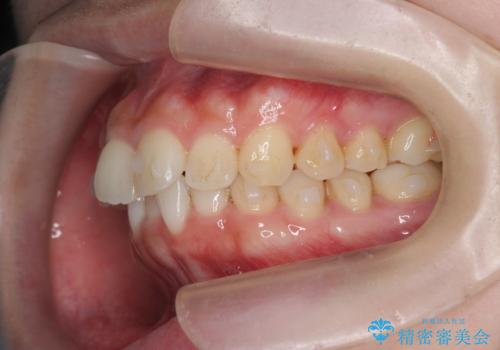

マウスピース 狭窄歯列の改善

- 噛み合わせが深い、笑った時の歯並びの改善を求めて来院されました。

マウスピース型の矯正装置インビザラインを用いた治療を計画します。

狭くなってしまった歯並びを放物線状に並べることで噛み合わせの安定・見た目の改善・ガタつきの改善を達成することができました。